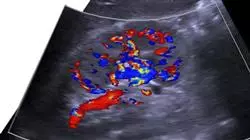

A evolução exponencial da Medicina Cardiorrenal melhorou a abordagem do manejo de doenças que afetam o coração e os rins. Dessa forma, os médicos podem se beneficiar de ferramentas e técnicas de diagnóstico que contribuem para uma avaliação precoce e precisa de danos cardíacos ou renais. Além disso, surgiram terapias inovadoras e multidisciplinares que melhoram os resultados e a qualidade de vida dos pacientes. Portanto, os especialistas são obrigados a identificar estes avanços para se posicionarem na vanguarda da área da saúde.

Considerando isso, a TECH desenvolveu este Programa avançado, que proporciona aos médicos o conhecimento mais atualizado na abordagem dos distúrbios cardiorrenais. Através de 450 horas de estudo, o aluno aprenderá em profundidade sobre o manejo de biomarcadores em pacientes que sofrem deste tipo de doença ou identificará procedimentos de alto nível para o tratamento da Insuficiência Cardíaca Aguda em pacientes com DRC.